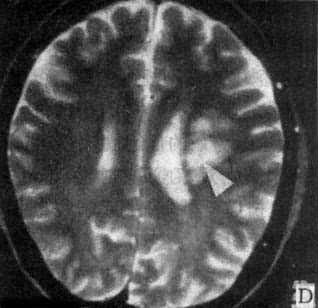

MRI 适宜于观察CT扫描为等密度的亚急性脑内血肿,已如前述。脑梗塞的发现MRI比CT扫描要早,一般起病后6小时MRI即可出现异常。脑干和小脑腔隙性梗塞灶的探测,MRI明显优于CT。脑梗塞灶在T1WI上呈低信号,在T2WI上呈高信号(图5-1-6C、D)。

在矢状面(A)和冠状面(B)T1WI可见垂体肿块向鞍上延伸,呈等信号区(→);在横断面T1WI(C)和T2WI(D)上分别可见左枕和右基底节区脑梗塞灶呈低和高信号区(→);在矢状面T1WI(E)和横断面T2WI(F)上,可见基底动脉瘤环形影,其内为低信号和高信号区,高信号区为瘤内血栓形成(→)